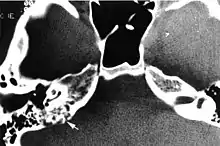

Imaging findings

Imaging studies help to identify the tumor and the specific anatomic site of involvement. Magnetic resonance images show a hyperintensity (hypervascularity) of a heterogeneous mass by T1 weighted images. Computed tomography shows a multilocular, lytic destructive temporal bone mass, centered on the vestibular aqueduct (between internal auditory canal and sigmoid sinus).[1][6][7]